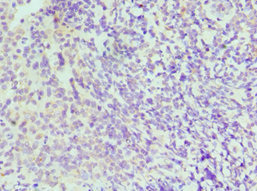

Immunohistochemistry of paraffin-embedded human colon cancer using CSB-PA011819ESR2HU at dilution of 1:100